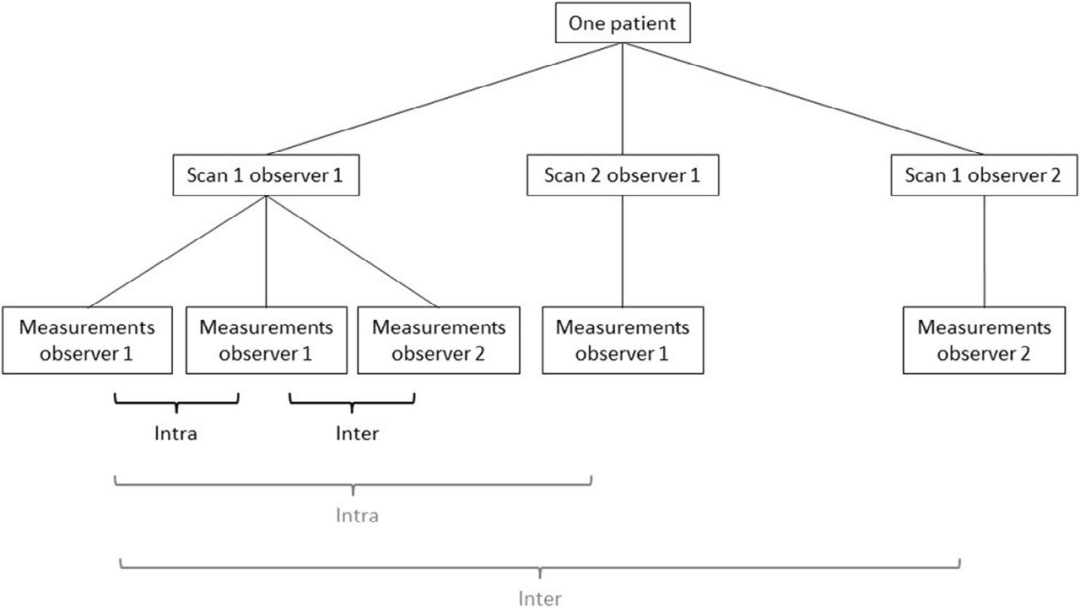

实验设置两名观察者(实验人员),分为两个阶段,第一阶段排除扫描过程的差异影响,观察者对一组扫描影像随机进行分析测量,实验的第二阶段将扫描过程的差异影响考虑在内,观察者扫描患者脊柱并直接对这些扫描影像进行分析测量。

每位患者总共接受三次Scolioscan®扫描。观察者1扫描两次,观察者2扫描一次,两名观察者分别对自己扫描一次的影像进行一次角度测量;至于观察者1额外扫描一次的影像,观察者1测量两次,观察者2测量一次。通过对测量结果的统计分析,研究团队在考虑(上图黑色标记)和不考虑(上图灰色标记)扫描差异的两种情况下分别衡量同一观察者两次测量之间以及两个观察者之间的差异性。